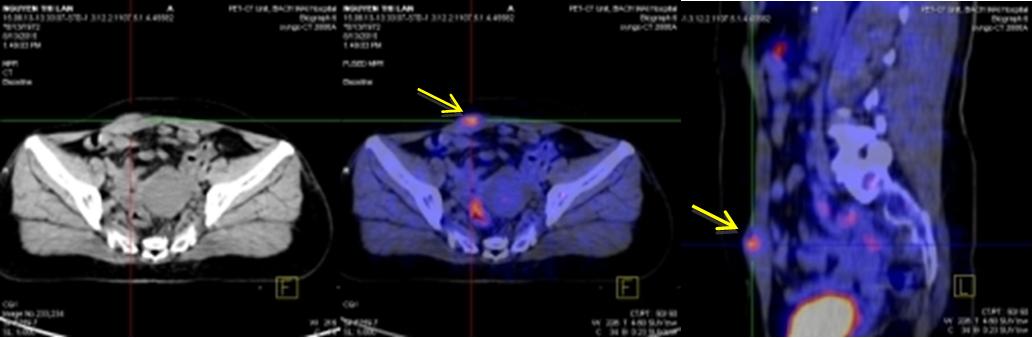

Kết quả chụp PET/CT:

Hình chụp PET/CT toàn thân

Hình ảnh nốt kích thước: 1,6x1,2cm vị trí 1/4 dưới trong vú phải

tăng hấp thu FDG, max SUV=2,8.

Hình ảnh niêm mạc tử cung tăng hấp thu FDG sinh lý trong chu kỳ kinh nguyệt, SUV=5,4.

Hình ảnh tổ chức thành bụng trước bên phải KT (1,8x1,2)cm tăng hấp thu FDG, max SUV=4,1.